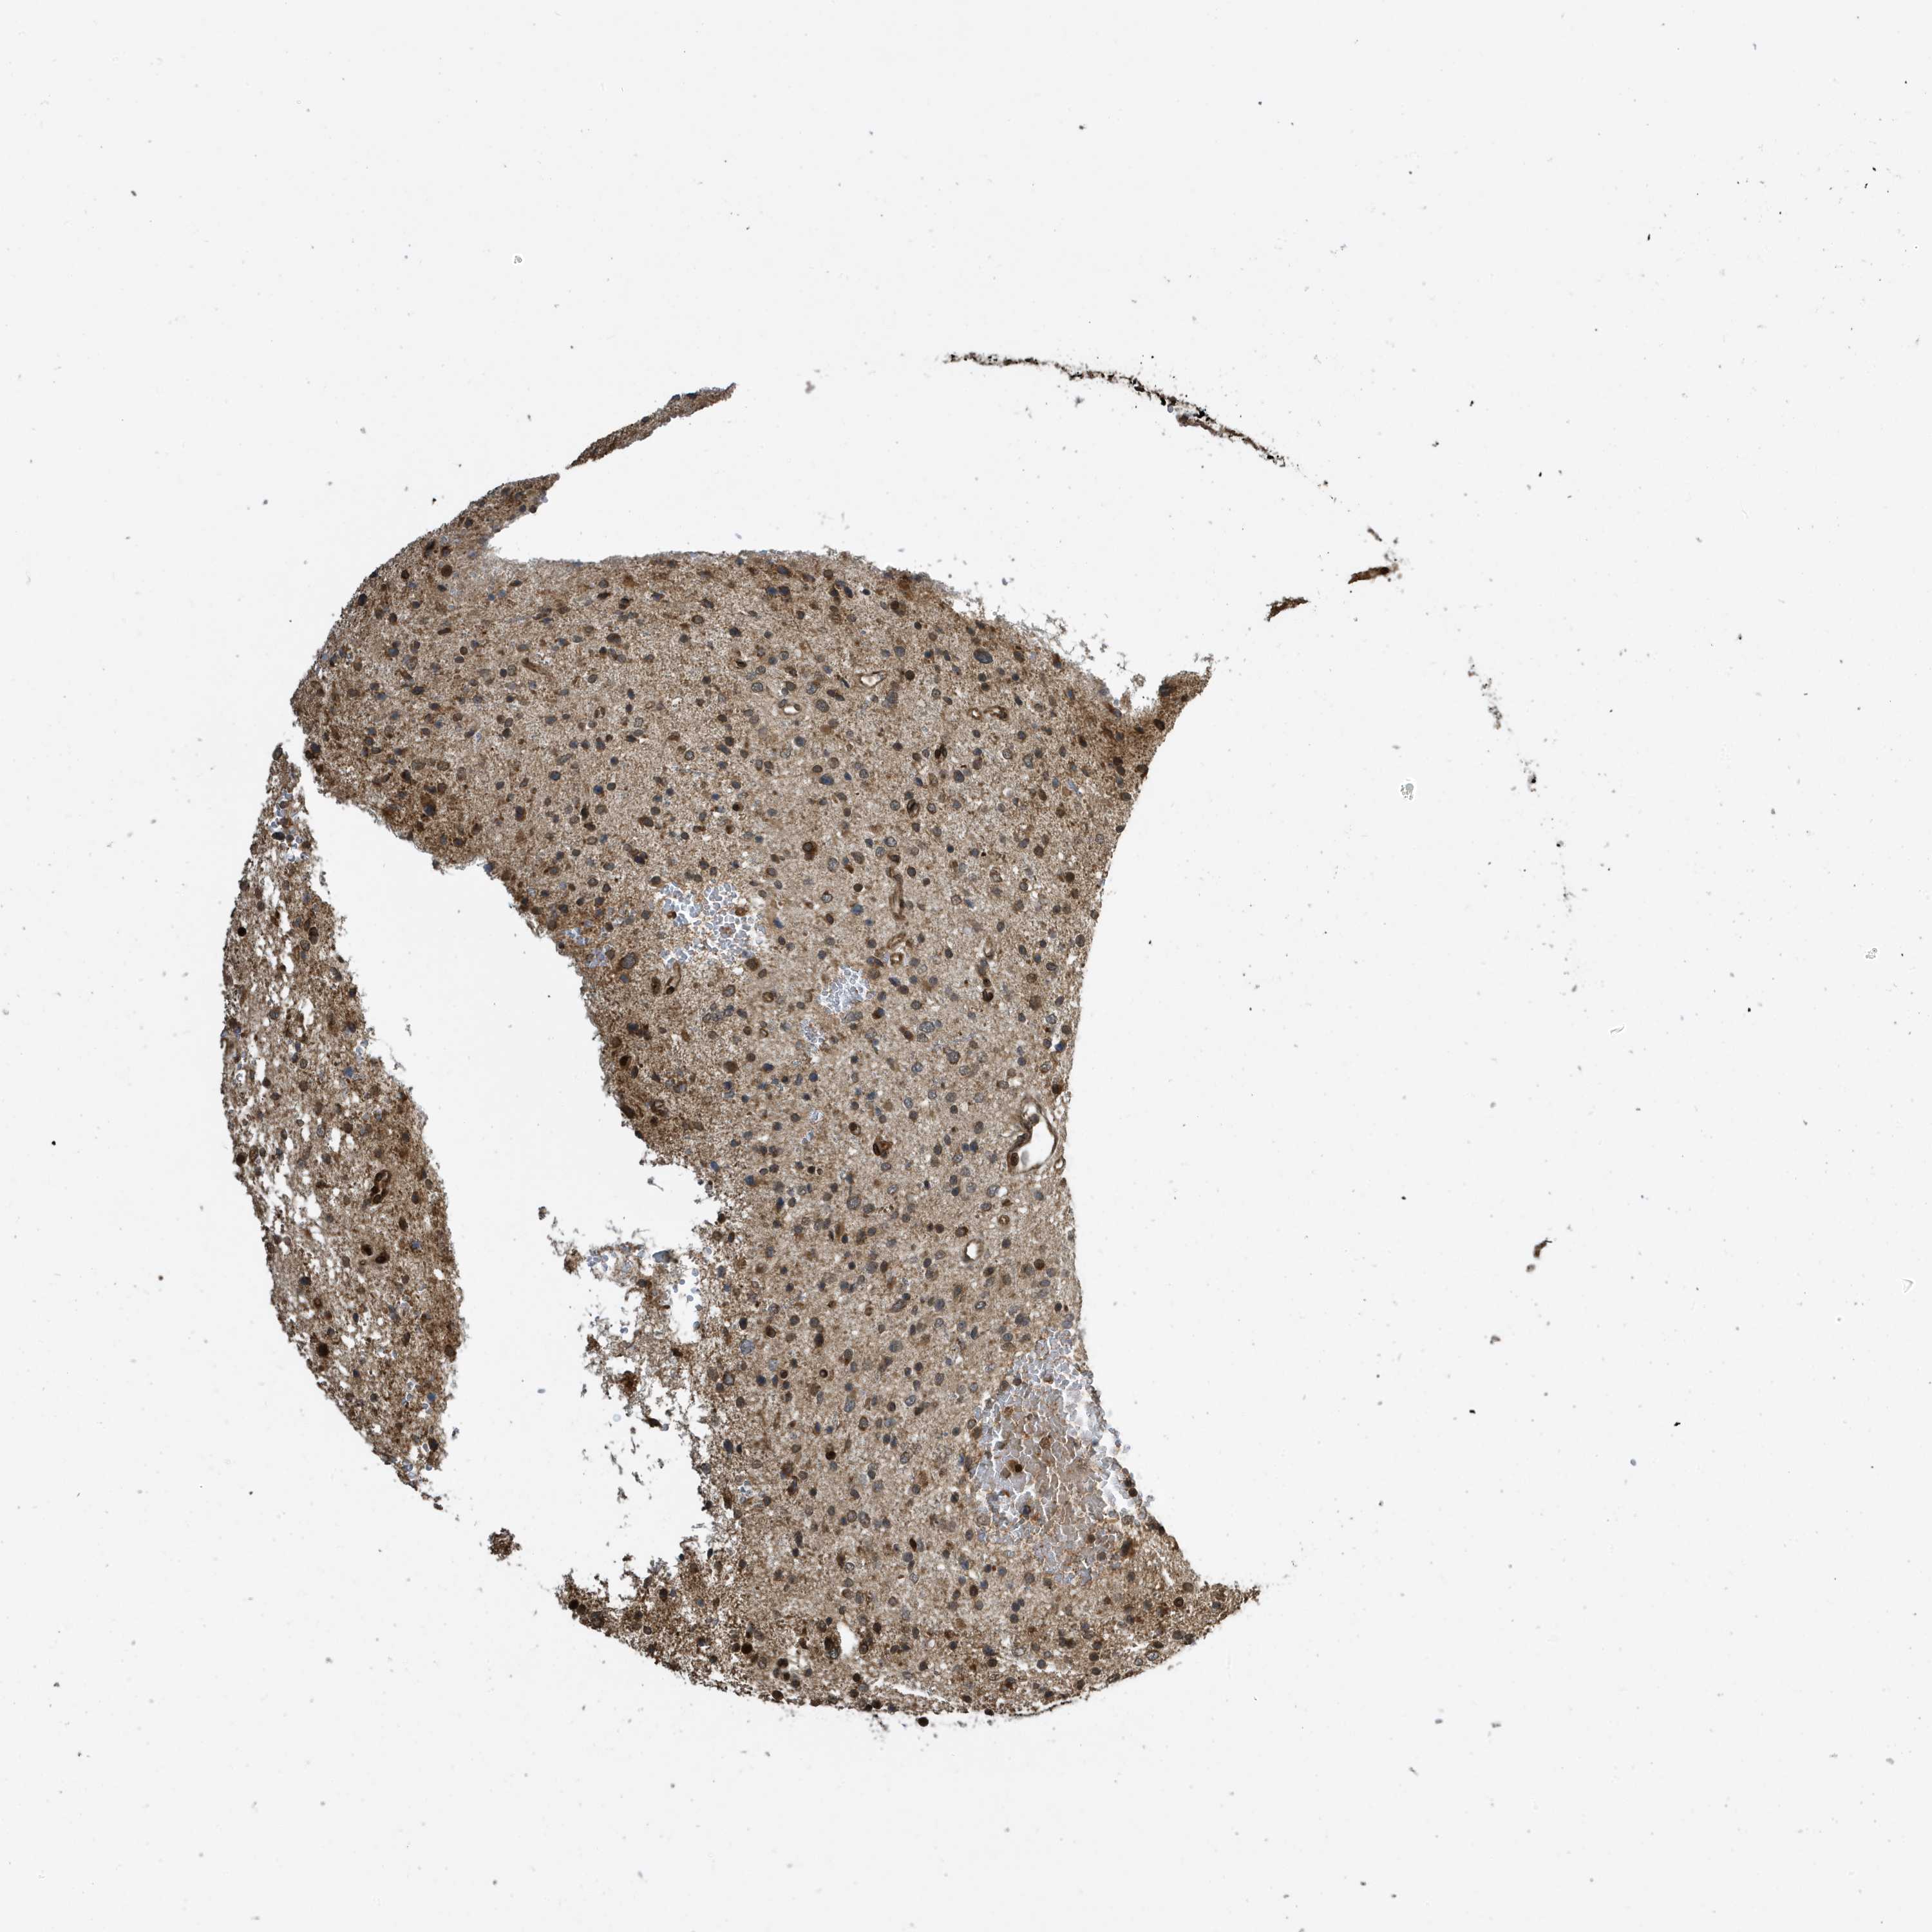

GLIOMA - Protein expressioni

A mouse-over function shows sample information and annotation data. Click on an image to view it in a full screen mode. Samples can be filtered based on level of antibody staining by selecting one or several of the following categories: high, medium, low and not detected. The assay and annotation is described here.

Note that samples used for immunohistochemistry by the Human Protein Atlas do not correspond to samples in the TCGA dataset.

Antibody stainingi

Antibody staining in the annotated cell types in the current human tissue is reported as not detected, low, medium, or high, based on conventional immunohistochemistry profiling in selected tissues. This score is based on the combination of the staining intensity and fraction of stained cells.

Each image is clickable and will lead to virtual microscopy that enables deeper exploration of all samples and also displays staining intensity scores, fraction scores and subcellular localization as well as patient and tissue information for each sample.

Antibody CAB034070

Staining

High

Medium

Low

Not detected

Intensity

Strong

Moderate

Weak

Negative

Quantity

>75%

75%-25%

<25%

None

Location

Nuclear

Cytoplasmic/membranous

Cytoplasmic/membranous,nuclear

Glioma, malignant, High grade

Glioma, malignant, Low grade